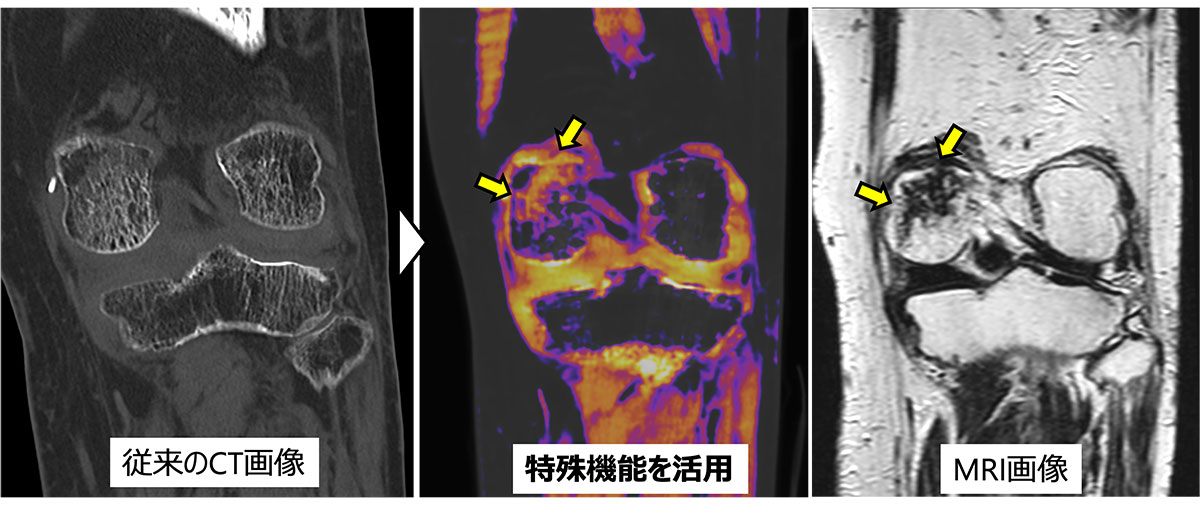

整形領域

✓ 細かな骨折を発見する高精細な画像を作成

整形領域では、骨折の有無やその重症度を把握するためにより詳細なCT検査が役立ちます。

整形領域では他の部位の検査と比較して低被ばくかつ短時間で検査が可能であることから、小児から高齢者まで安心して検査を受けていただけます。

CT撮影後は、診療放射線技師が「MPR画像」や「3D画像」と呼ばれる高度な画像を作成することで、骨折の程度を正しく判断し、患者説明や手術の際に役立てています。

膝のCT画像。従来はMRIでしか発見できなかった病変(

)に対して、

特殊な撮影とカラー表示を組み合わせることで病変を写し出した。

膝MRI

整形領域のMRI撮影では、骨折や靭帯の損傷の描出に優れています。膝の検査では、半月板や靭帯損傷の具合やその予測も可能です。また、出血・炎症・腫瘍の有無・骨の中の状態なども確認できます。

当院のMRI装置では、靭帯や軟骨の描出能が格段に上がり高精細な画像を得る事ができるようになりました。

微細な損傷も抽出でき、より病態に合わせた適切な治療を検討できるようになりました。